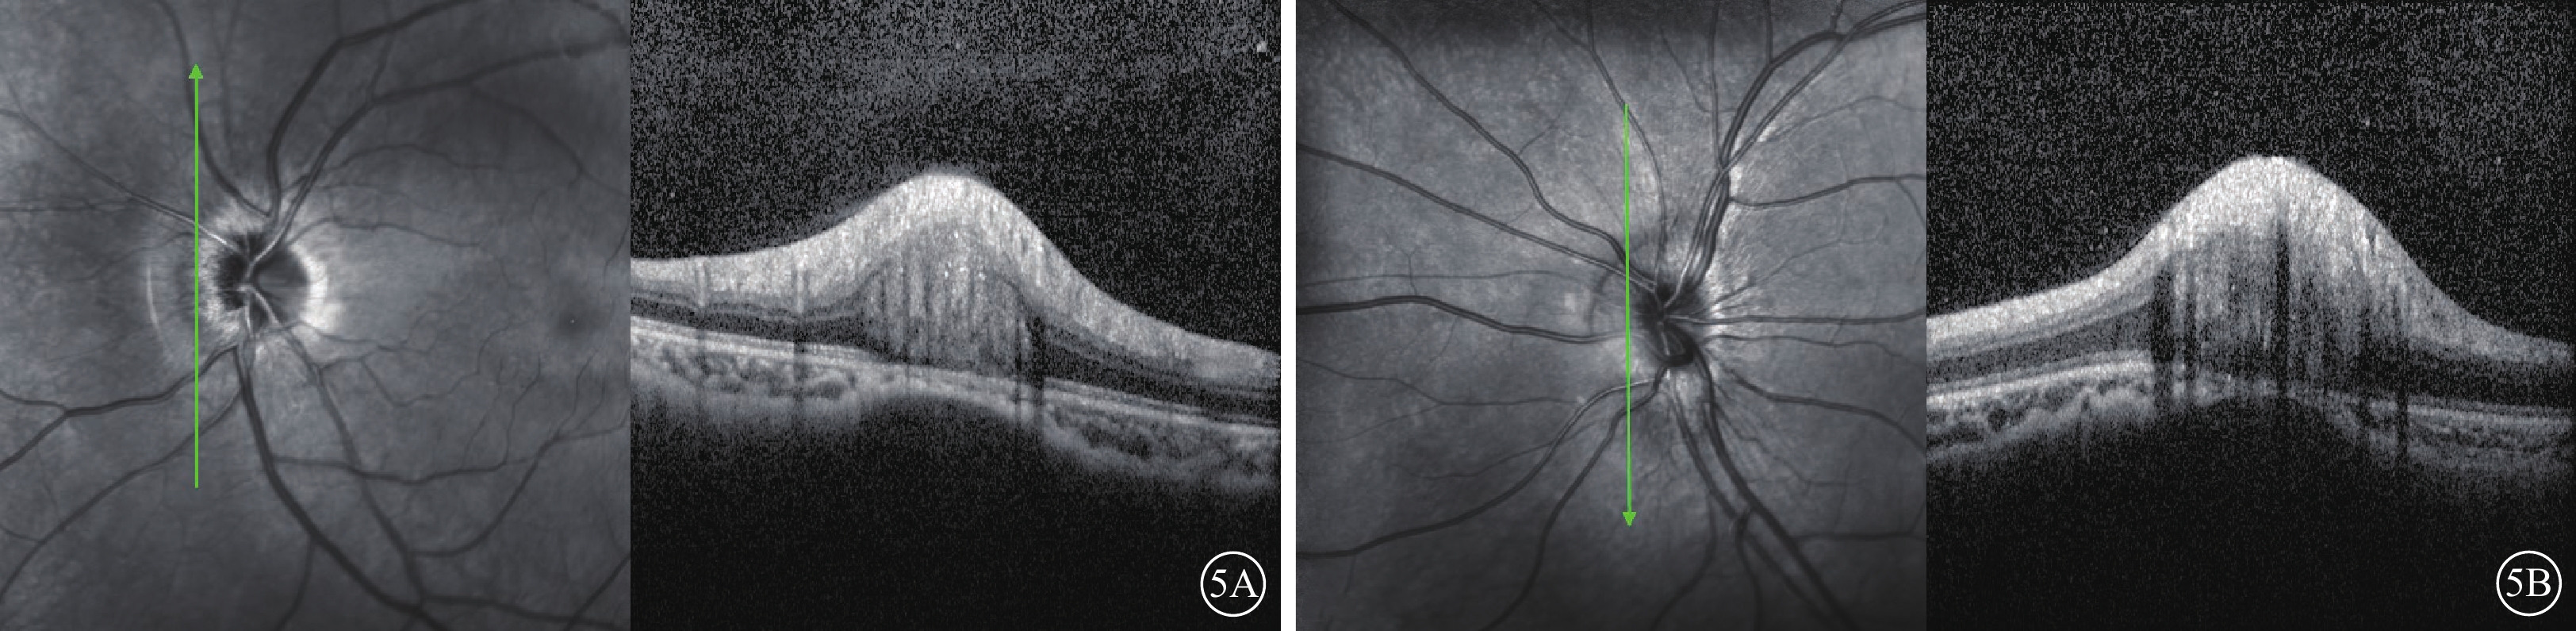

OCT檢查,垂直視盤中央單線或星形掃描模式掃描,僅可見視盤不同程度隆起(圖3);加密精細掃描模式,連續向視盤鼻側擴大掃描,可見與眼底彩色照相盤周鼻側水腫對應部位側向突入視網膜神經纖維層下、Bruch膜上,邊界清晰卵圓形稍強反射結構(圖4),且水腫程度越高其體積相對越大(圖5)。黃斑區視網膜RPE層及神經節細胞層厚度均未見明顯異常。